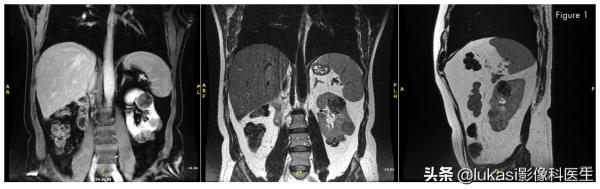

如今,超聲(US)、CT (CT)和MRI顯示孤立的左腎中至少有11個腎腫瘤,最大的完全外生,上極4.2cm,下極4.7cm和3.7cm。沒有中樞腫瘤或累及腎竇、腎靜脈或腔靜脈。與患者討論了選擇:明確的腹腔鏡根治性腎切除術,幾年後透析和腎移植,或計劃的保守手術。他決定採取保守的方法。行左側經腹腔腹腔鏡根治性腎輸尿管切除術。腎完全鬆解後,用聚合物夾近端雙夾住動靜脈並切斷。在經髂血管水平切斷輸尿管。透過髂窩切口將腎臟取出,儲存在冰泥中,並持續灌注冷儲存移植液。在超聲檢查的幫助下,我們進行了保留腎單位的手術,切除或摘除所有腫瘤以最大限度地保留正常實質。用可吸收的縫線和止血劑對切開的腎盞進行修復和精細重建。用吉布森右切口進行自體移植。重建腎在腹膜後自體移植,血管軸在髂外靜脈和動脈內吻合。輸尿管採用LichGregoir體外抗反流手術,採用雙J支架植入膀胱。

沒有右腎,僅存左側孤腎,可見多發腫瘤。

腎臟腫瘤切除,並進行重建,準備自體移植

在左腎切除的大小不等的13個腫瘤